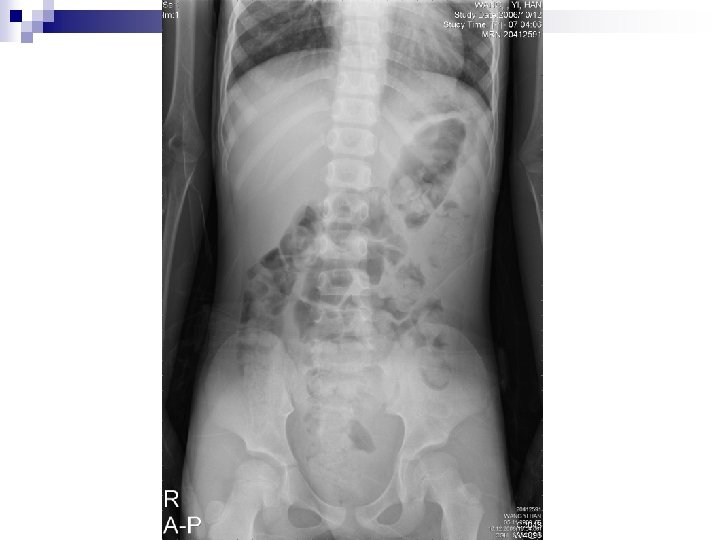

Lab exam 20: 18 CBC-DC, sugar, CRP, BUN, Cr, Na, K, ALT n KUB n